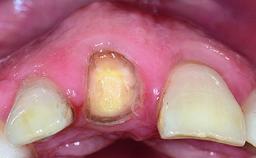

Replacement of an Ankylosed Central Incisor with a Gingival Recession: Tooth Extraction with Socket Grafting and Late Implant Placement with Simultaneous Contour Augmentation

In 2008, a healthy 15-year-old female, non-smoking patient presented at our clinic with a major esthetic problem of tooth 21. Her dental history revealed that the tooth had been avulsed by trauma years before. As a result, the replanted and temporarily splinted tooth had ankylosed and was in severe apical malposition. The ankylosed tooth exhibited a significant gingival recession that disturbed the patient greatly. Due to the patient’s low age and with her skeletal growth not completed, periodic follow-up visits were scheduled to monitor the situation until the patient was old enough for implant therapy.

Bone Volume Deficient vertically or deficient vertically AND horizontally